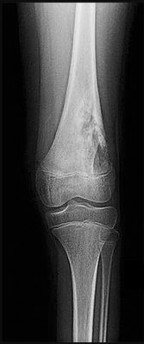

Figures 5a and 5b are the radiographs of a 74-year-old man with poorly differentiated squamous cell carcinoma of the lung. He has had an uneventful recovery after undergoing a wedge resection of his left upper lobe 6 months ago. He is experiencing left lateral knee pain, and a whole-body positron emission tomography/CT scan shows no avid area other than the lateral left distal femur. This patient has needed to use a wheelchair for 3 weeks because of his pain. You discuss these treatment options: aggressive curettage, local adjuvant treatment, cementation, and prophylactic fixation vs distal femoral resection and megaprosthesis total knee arthroplasty reconstruction. You should tell him that

Distal femoral megaprosthetic reconstruction after tumor resection is a reliable oncologic procedure, but 5-year implant survival is as low as 74% with an approximate 8% deep infection rate. The amputation rate is as high as 8% because of infection or recurrence, and there is an overall 18% revision rate. More than 10% of distal femoral megaprosthetic reconstructions are performed to address metastatic disease.

Fixation failure and infection may occur with either procedure. Radiation may not be recommended after a megaprosthesis reconstruction unless margins are not free of tumor. Either operation may be equally successful in returning patients to functional activities. Overall disease-free survival is related to the aggressiveness of the tumor and not the type of reconstruction performed.